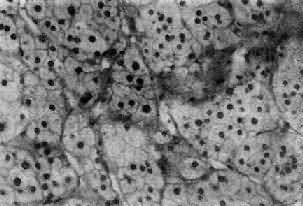

三、肾上腺肿瘤(一)肾上腺皮质腺瘤 肾上腺皮质腺瘤与局灶性结节性增生的病变相似,两者可以并发。腺瘤通常是单侧单发性,并有薄层包膜,对周围组织有压迫现象,为鉴别的主要点。大小直径为1~5cm,切面黄色,有时呈红褐色,镜下多为类似束状带的泡沫状透明细胞,含有丰富类脂质,有时由类脂含量少的嗜酸性细胞构成,或者两种细胞混合存在。瘤细胞排列成团,由含有毛细血管的少量间质分隔(图15-16)。部分腺瘤为功能性,可引起醛固酮增多症或Cushing综合征,在形态上与非功能性腺瘤没有区别。

图15-16 肾上腺皮质腺瘤 上图 下图 (二)肾上腺皮质癌 肾上腺皮质癌(adrenocortical carcinoma)甚少见,一般为功能性,发现时一般比腺瘤大,重量常超过100g,呈浸润性生长,正常肾上腺组织破坏或被淹没,向外侵犯周围脂肪组织甚至该侧肾。小的腺癌可有包膜。切面棕黄色,常见出血、坏死及囊性变。镜下分化差者异型性高,瘤细胞大小不等,并可见怪形核及多核,核分裂像多见(图15-17)。常转移到腹主动脉淋巴结或血行转移到肺、肝等处。分化高者镜下像腺瘤,如果癌体小又有包膜,很难与腺瘤区别,有人认为直径超过3cm者,应多考虑为高分化腺癌。